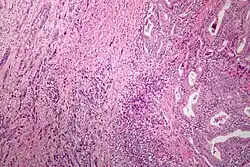

| Microscopic image of anaplastic thyroid carcinoma. H&E stain. | |

Anaplastic tumors have a high mitotic rate and frequently invades the local blood and lymphatic vessels.[5] Cellular death is frequently visualized on microscopic images.[2] The presence of regionally swollen lymph nodes in older patients in whom needle aspiration biopsy reveals characteristic vesicular appearance of the nuclei supports a diagnosis of anaplastic carcinoma. Microscopic images of ATC usually show inflammatory cells from the immune system such as T cells and macrophages.[2]